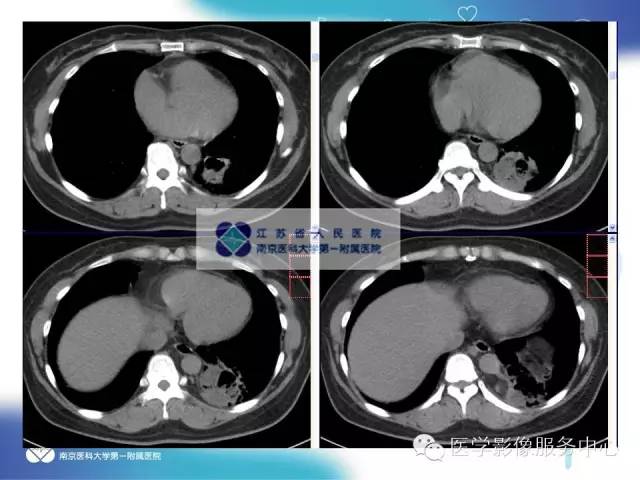

【病例】肺隔离症1例CT影像表现

女性,36岁。反复发热、咳嗽、咳痰一年。

CT:主要表现为三种类型:含有气体和液体的囊肿或软组织肿块;围绕囊肿或肿块周围的肺气肿改变;局限性肺多血管征。病变周围肺组织还可伴有支气管扩张,肺组织实变等。增强扫描病变实质可见轻度或明显不规则强化,囊性病灶可见环形强化,结合图像后处理技术( MPR、MIP、VR)多可见异常供血动脉及引流静脉,在一定程度上可以取代动脉造影。隔离肺组织供血动脉多为胸主动脉和腹主动脉,少数为隔下动脉、肋间动脉、脾动脉等。引流静脉多为肺静脉。